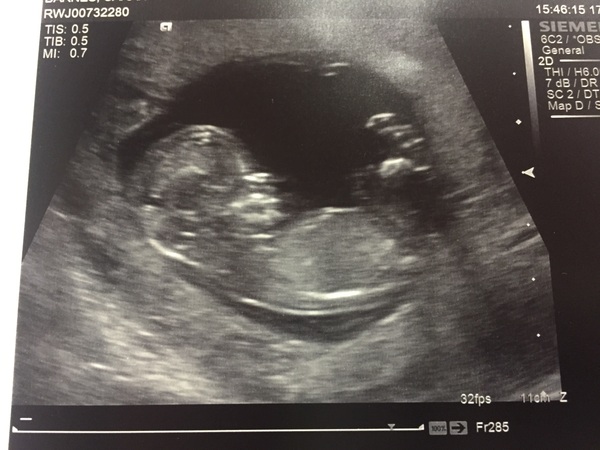

I had my scan yesterday and there was one very fidgety wriggly baby in there! Lovely to see! Moved forward a few days as well - bonus - EDD 20/05/2017. Great to see everyone's scans and that so many are feeling better as well.

Had dating scan attempt two today, as the first one had been booked too early and they couldn't do all the measurements.

Wriggly little baby there, all seems fine, NT measurement 2.4 at the widest but still have to wait until Tuesday at least when they will tell me if I'm high risk. Otherwise ten days at least for the low risk letter. Argh the waiting game never stops does it. I really wanted to finally tell everyone and out my bump as I'm running out of ideas how to hide it.

Due date brought forward to 23 May.

So relieved that everything looks fine, eeee I have a little baby in my belly and I'm starting to think that this is actually going to happen!

Fox - I think I'm the last and had it today. EDD put back a day to 29th May. Apparently everything looked ok Smile

I am still waiting for my 12w scan! It is this afternoon at 3.15, I am very nervous. I am still feeling sick which is a good sign but I won't relax until I see that everything is ok. Is anyone else yet to have their scan or am I the last? My edd is 31 May so feel quite behind in this group Smile